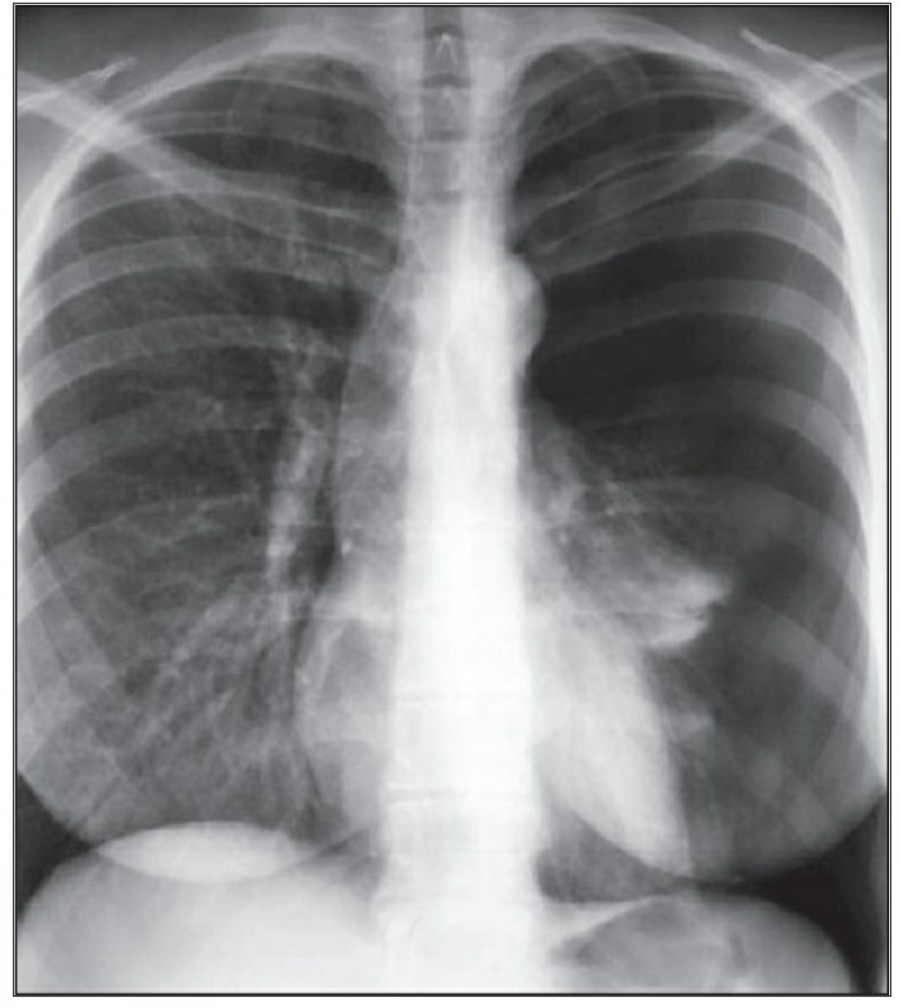

방사선 소견상 Pleural effusion은 환자 흉부의 dependent area에 고인다. Erect position에서 확인하기가 쉬운데, 폐의 base에 고임으로써 costophrenic angle blunting을 보이고 lower lobe vessel들의 흐리게 한다. Supine position에서는 확인이 더 어려운데, pleural fluid는 posterior basilar space에 고여서 폐 base 쪽으로 intensity가 증가하는 homogenous density를 보인다. 정상적인 bronchoalveolar marking은 이와 같은 veil-like density 안에서 확인 가능하다. Fluid 양이 늘어나면서 diaphragm의 윤곽이 흐릿해지고 costophrenic angle도 없어지는데, 이 costophrenic angle blunting이 없더라도 pleural space에 1L 정도의 pleural fluid가 있을 수 있다는 것을 기억해야 한다. 그 양이 더욱 늘어날 수록 fluid는 lung의 apex에서 pleural cap으로 나타날 수 있으며, 이는 supine position에서도 확인 가능하다. Pleural fluid는 lung의 medial side에 고일 수도 있으며 이는 mediastinum의 확장으로 보일 수도 있다.

적은 양의 pleural fluid는 꼼꼼히 확인하더라도 supine radiograph에서 놓칠 수 있는데, 만약 chest X ray에서 보이지 않지만 임상적으로 의심이 되는 경우에는 lateral decubitus film으로 확인해 볼 수 있다. Fluid는 dependent position에 고이므로 환자를 의심되는 방향으로 옆으로 눕혀야 한다. Lateral decubitus film은 적은 양의 pleural fluiid는 물론이고 loculated effusion과 free effusion을 확진하는 데도 도움이 된다. 특히 loculated effusion은 한 개 이상의 drain이 필요할 수 있으므로 pleural drainage를 고려할 때 특히 중요한 검사이다. 중환자에서 흔하게 나타나는 subplumonic effusion은 lung base에 존재하는 pleural effusion을 말하는데, chest X ray 상에서 raised hemidiaphragm with flattening and lateral displacement of the dome 형태로 나타나며, lateral decubitus film이 도움이 된다.